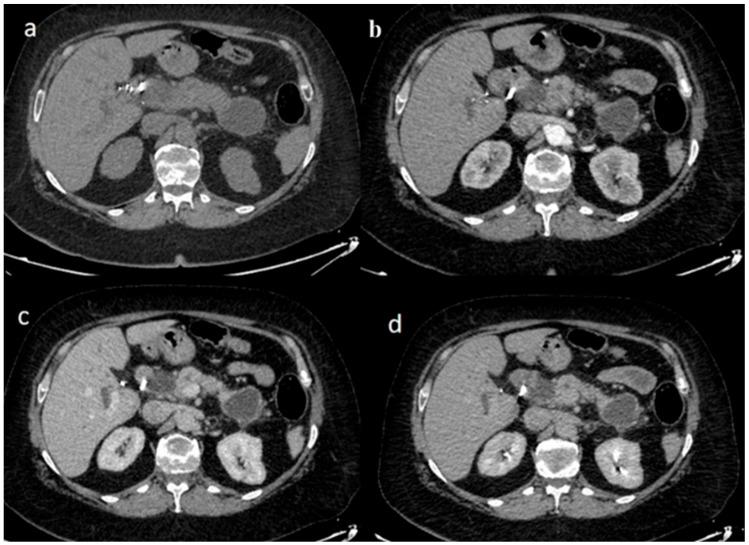

胰腺导管腺癌(PDAC)是最常见的胰腺恶性肿瘤,其特征是预后非常差。很少有患者会同时发生PDAC和另一种不同的原发性胰腺肿瘤,如胰腺神经内分泌肿瘤。本系统综述汇总了已发表的病例报告,描述了同时患有PDAC和其他胰腺恶性肿瘤患者的临床表现、影像学特征、治疗及预后。:对PubMed和Scopus进行全面检索,确定了26篇相关病例报告,纳入标准侧重于组织学确诊的同时性胰腺肿瘤,并排除转移性疾病。:大多数患者有两个胰腺病变,通常位于胰腺体部和尾部。诊断性成像检查方法,如计算机断层扫描和内镜超声,显示出常见的表现。肿瘤标志物,特别是CA 19-9,通常会升高并有助于诊断。手术方式也根据肿瘤位置和分期而有所不同,手术范围从惠普尔手术到全胰切除术。术后经常采用化疗。值得注意的是,淋巴结受累和肿瘤体积较大与预后较差有关。:总之,这些患者可能表现出常见或不常见的临床症状以及实验室和影像学检查结果,构成了一个重要且独特的诊断和治疗挑战。

https://cdn.ncbi.nlm.nih.gov/pmc/blobs/81ff/12194590/f0ed9310b5ae/jpm-15-00221-g003.jpg